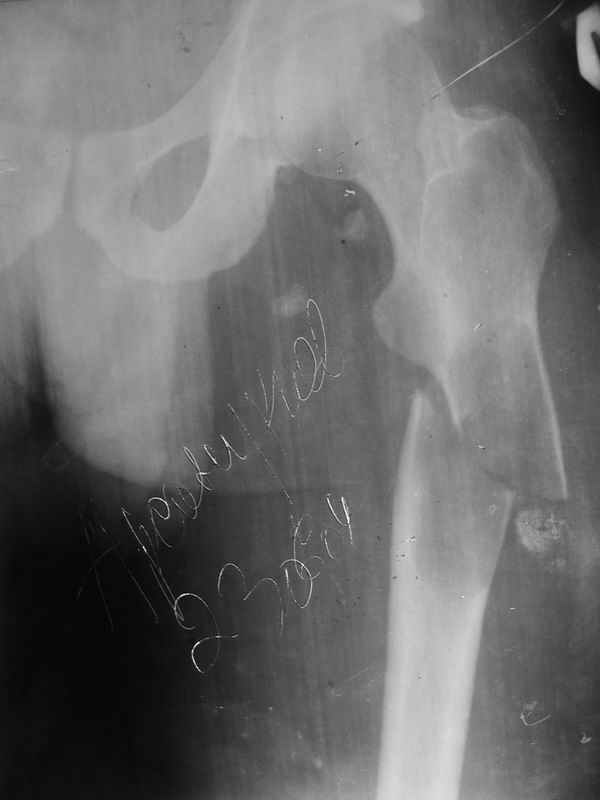

Добрый день, уважаемые коллеги!Мои коллеги из Грозного просили проконсультировать случай больного М. 26 лет. Боли беспокоили около 1 года в области подвздошной ости слева, по поводу чего неоднократно обледовался - неоднократно выполнены снимки тазобедренного сустава. Снимки бедра не выполнялись. 1,5 месяца назад, находясь на работе, поднимаясь по лестнице в больнице почувствовал сильную боль, упал. При этом произошел перелом верхней трети бедра. На рентенограммах, представленных во вложении обнаружен патологический перелом. Траматологи расценивают это как кистозную дисплазию, хотя уверенности нет. Сейчас находится на склетном вытяжении. Каков прогноз заболевания? Верна ли тактика, показаны ли в будущем какие-то вмешательства?Заранее спасибо.С наилучшими пожеланиями, Бекхан.

Уважаемый Бекхан! По клинике и рентгенограммам (на снимках 1010139 и 1010140 прослеживается козырек) у пациента более всего вероятна опухоль Кодмана (морфологический характер можно уточнить по биопсии).

Для хондробластом, насколько мне известно, не характерна ни диафизарная локализация, ни рентгнологическая картина, демонстирирующая инвазивный рост.

По представленным рентгенограммам процесс очень смахивает на юношескую дистрофическую костную кисту. Попробуйте дождаться частичной консолидации патологического перелома и сделайте пункцию очага - Вы ничем не рискуете. В полости скорее всего окажется кровь без давления. Одномоментно производится биопсия стенки очага режущим шлямбуром. Гистологическое подтвеждение наличия дистрофического процесса позволит Вам в дальнейшем выполнить аллопластику полости кисты с предварительной корытообразной резекцией (см. Волков М.В). Местоположение очага очень характерно для ЮДКК.

Да, костные кисты там бывают, но представленное их не сильно напоминает.

На мой взгляд, рентгенологическая картина все же напоминает солитарную кисту. В похожей ситуации мы выполнили (на фоне патологического перелома) васкуляризованную аутопластику малоберцовой костью на сосудистых анастомозах. Наблюдаем уже более 2 лет. Нагрузка на конечность в полном объеме, боли отсутствуют (рентгенограмма в аттачменте).

Na pervom meste- Solitary bone cyst

na vtoroe ja bi postavil Aneurismal bone cyst